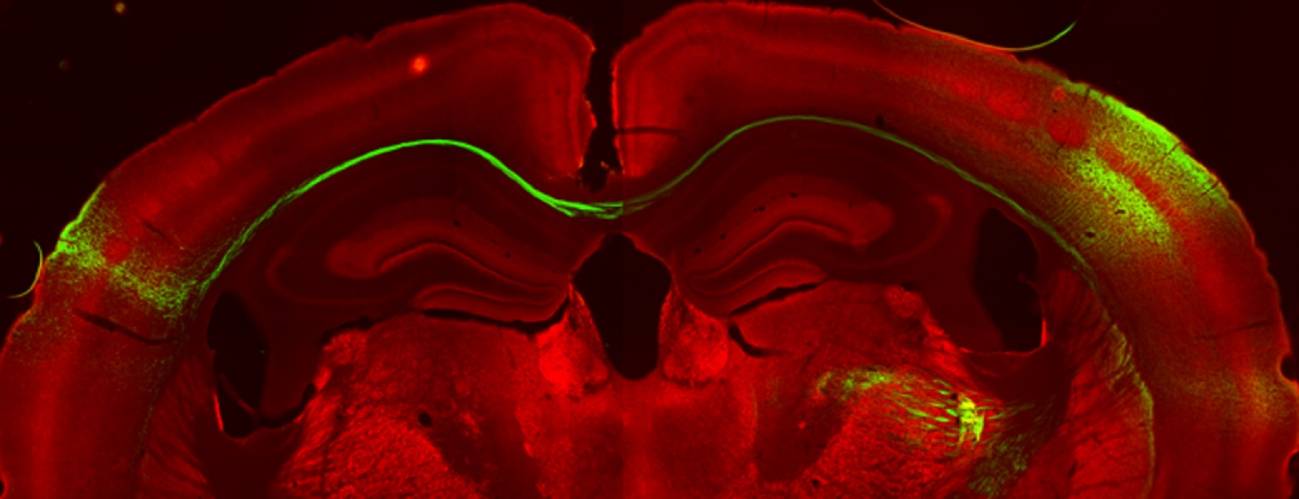

Investigadores del laboratorio dirigido por Ramón Reig en el Instituto de Neurociencias (IN), centro mixto del CSIC y la Universidad Miguel Hernández de Elche, han llevado a cabo un trabajo que ha confirmado, mediante estudios fisiológicos, que se produce una doble representación entre hemisferios que permite la percepción de continuidad, sin interrupciones entre ambos lados del cuerpo.

Hasta el momento, se había observado la presencia de esos axones, pero los investigadores del IN han demostrado en ratones las propiedades funcionales de esos axones que cruzan y hacen sinapsis con el otro hemisferio. Estos conectan especialmente información táctil de las partes de la línea media y generan una representación o activación idéntica de la información en ambos lados, permitiendo procesar la información sensorial de manera continua.

Centro sensorialEn este trabajo, cuyo primer autor es Roberto Montanari, han conseguido describir de forma precisa el circuito completo que comunica ambos hemisferios cerebrales: la información percibida ante un estímulo sensorial viaja a través del cuerpo calloso y es procesada específicamente en una región muy concreta de la corteza somatosensorial primaria, en el ratón los barriles de la fila A (RowA). Por lo tanto, estos representan un centro sensorial para la comunicación interhemisférica.

Además, han constatado que la información viaja a través de un carril concreto. La corteza cerebral que codifica la información táctil del ratón se divide en filas y columnas, y cada una de ellas contiene grupos de neuronas que se denominan "barriles".

ara validar estos resultados, el equipo imitó lo que había llevado a cabo, a nivel sensorial, en los bigotes del ratón con técnicas de optogenética. El experimento consistió en estimular directamente con luz la corteza cerebral para observar la respuesta de las neuronas de las filas A y, efectivamente, observaron que la respuesta coincidía y daba lugar al mismo fenómeno.